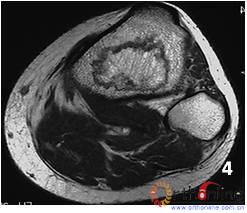

(二) 共分5型,各型的特点为:(图5)

图 5 中日友好医院依三柱结构对股骨头坏死的分型

Fig 5 China-Japan Friendship Hospital (CJFH) Classification for ONFH based on three pillars

1. M型(内侧型):坏死灶占据内侧柱,中央和外侧柱存留。

2. C型(中央型):坏死灶占据中央柱和内侧柱,外侧柱存留。此型中可见部分患者的坏死灶仅占据内侧柱的一部分,而另一部分内侧柱可存留。

3. L型(外侧型):坏死占据内、中、外三柱,但有不同情况,可分为三个亚型。

(1) L1型(次外侧型):坏死占据三柱,但外侧柱部分存留,至少应有皮质存留。

(2) L2型(极外侧型):坏死灶仅占据外侧柱或另加一部分中央柱,中央柱另一部分和内侧柱全部存留。

(3) L3型(全头型):坏死带穿透整个股骨头的外、中、内三柱的皮质及骨髓。